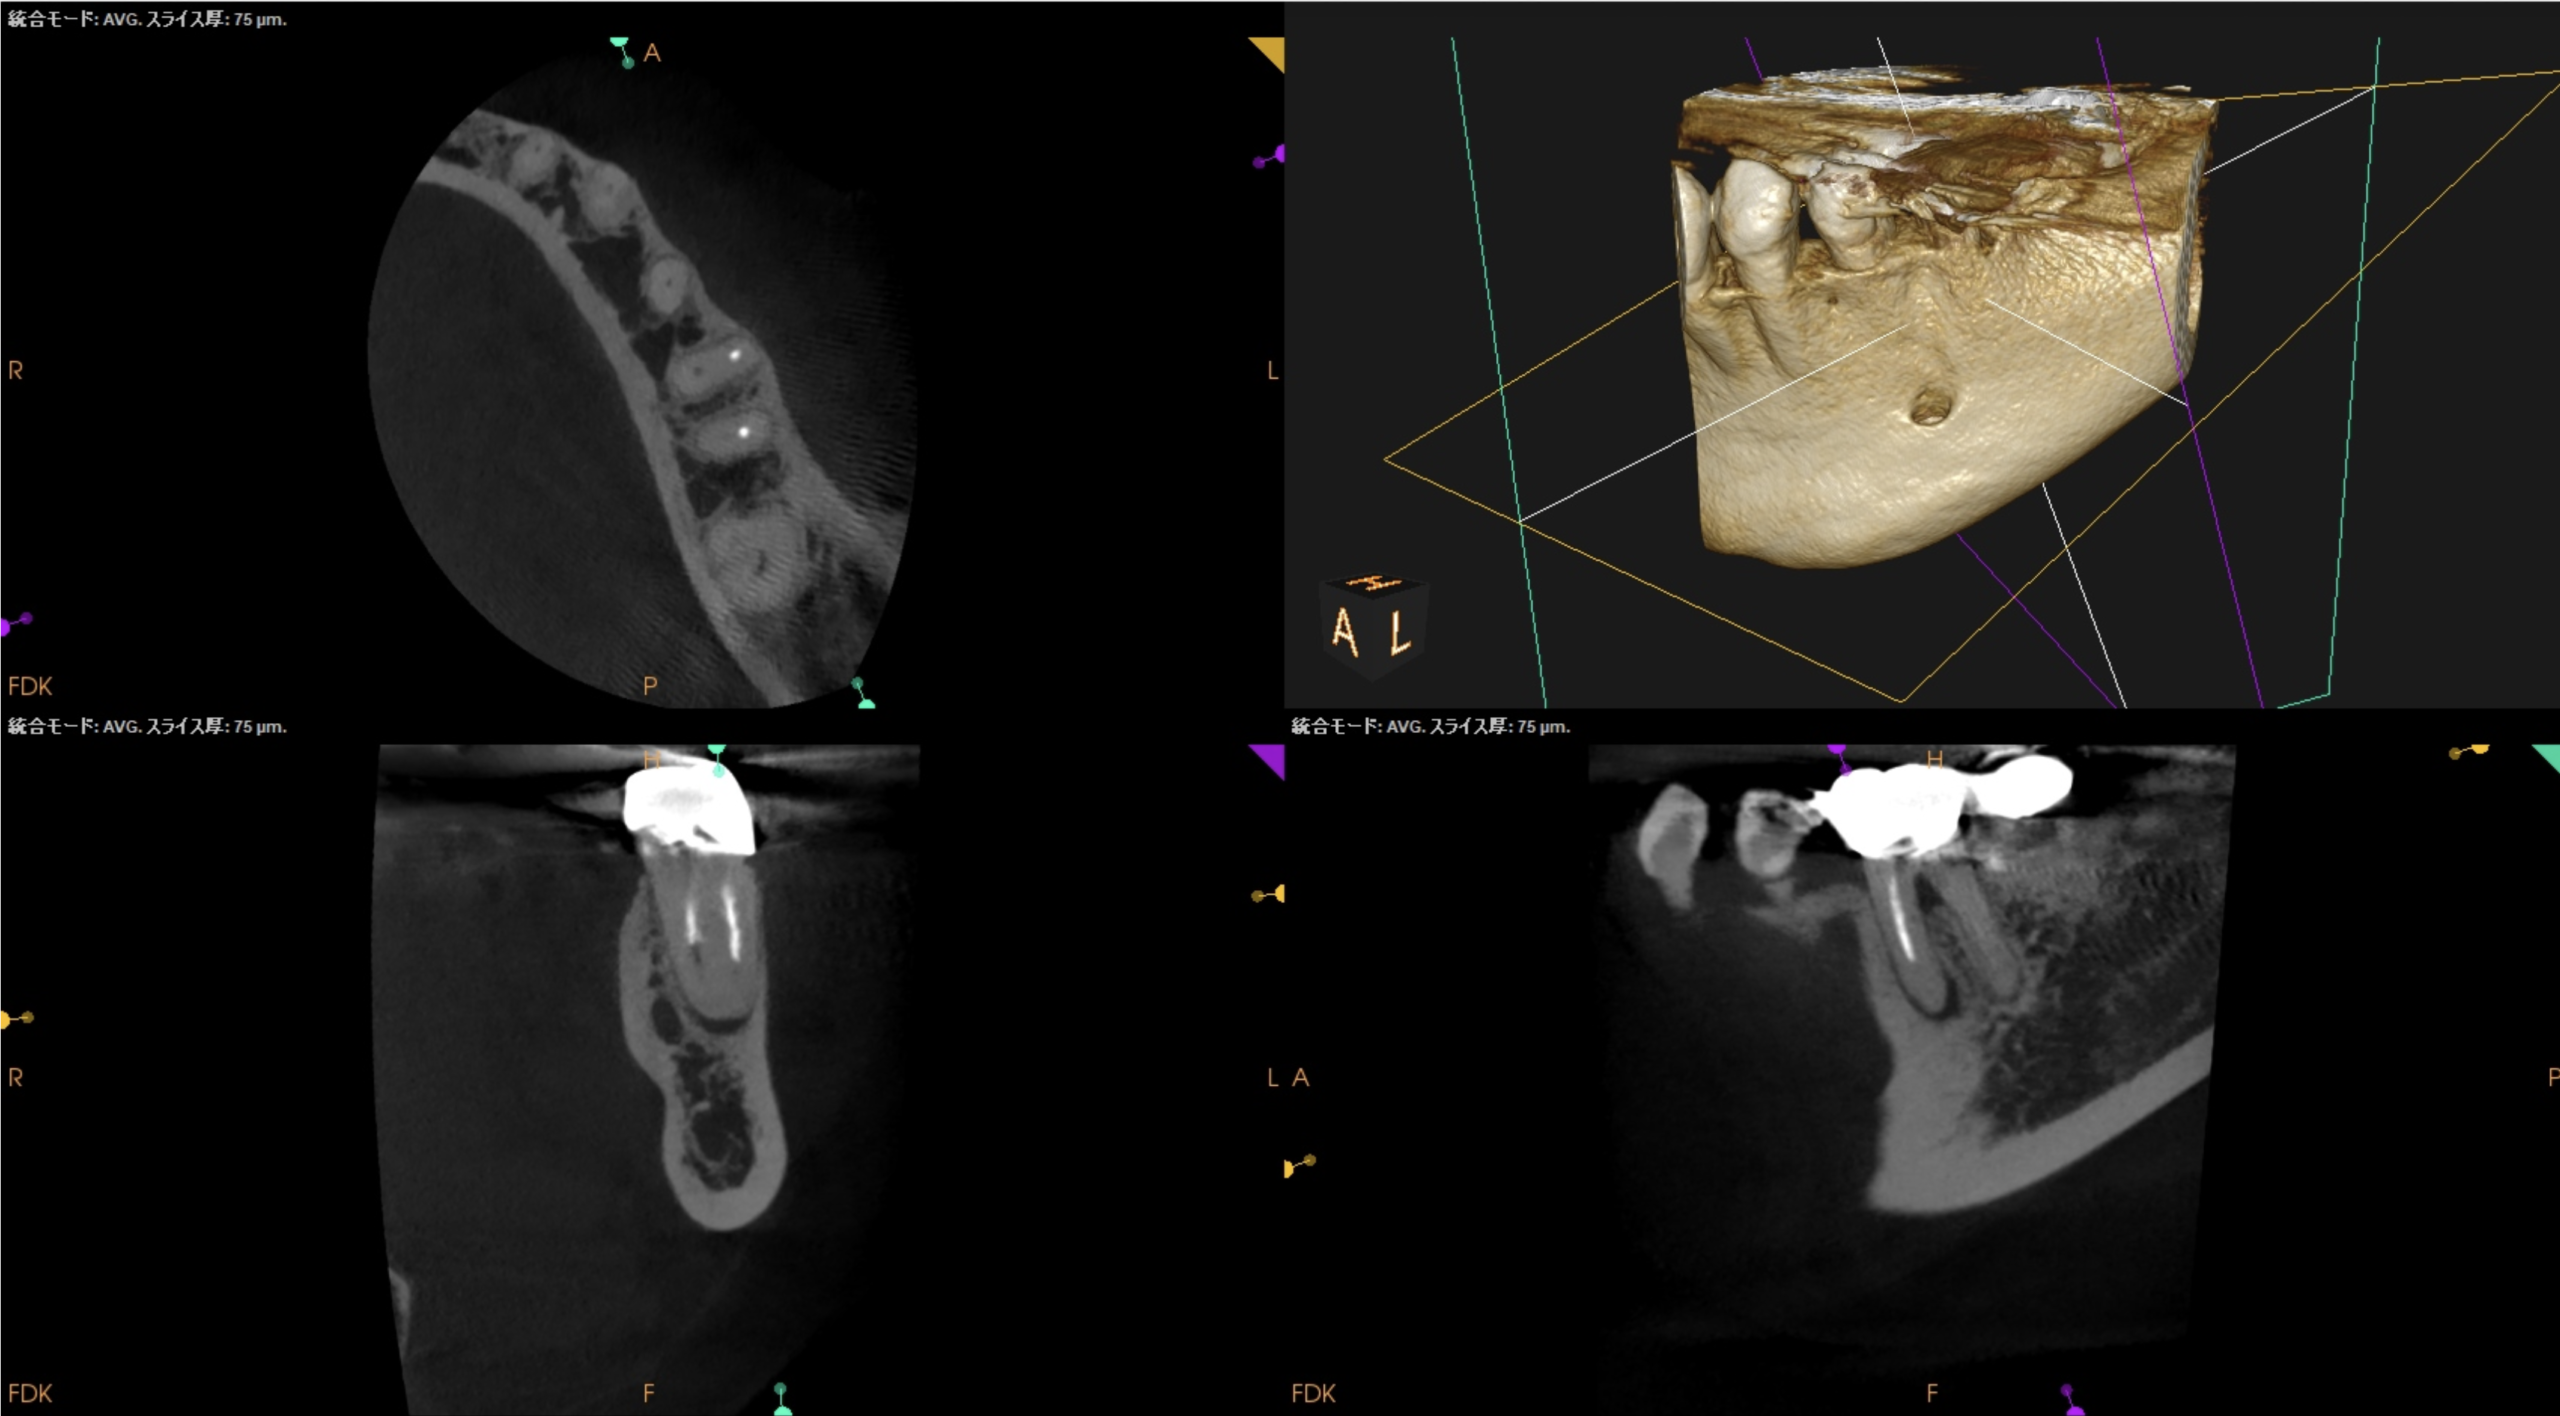

CBCTも撮影した。

CBCT(2025.10.31)

#19

MB

ML

D